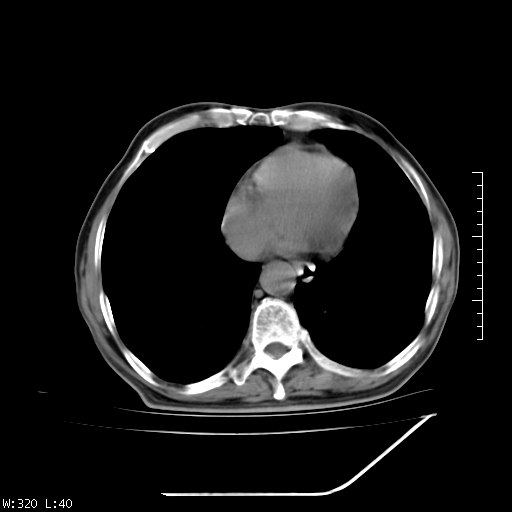

标题: CT23994:男、72、咳嗽、气短两月余,近来消瘦。 [打印本页]

标题: CT23994:男、72、咳嗽、气短两月余,近来消瘦。

右上肺大片状密度增高影,与胸膜关系密切,内见低密度透亮影,胸膜下可见三角形不张影,左下肺沿支气管走形结节影,纵膈内淋巴结显示。考虑结核并疤痕性不张可能性大,建议穿刺活检,排除肺泡癌。